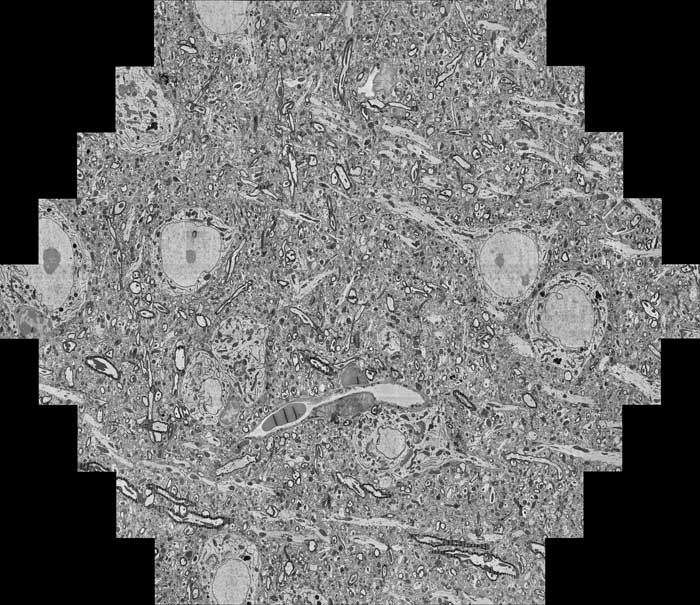

multi-beam_mouse-brain

multi beam image of mouse brain

Das mSEM nutzt 91 parallel arbeitende Elektronenstrahlen und ermöglicht so eine ultraschnelle, hochauflösende Abbildung selbst makroskopischer Objekte im Nanometermaßstab. Die Technologie ist ideal für die Analyse von Halbleiterchips, Nanomaschinen, biologischen Gewebeproben oder komplexen Organstrukturen wie dem Gehirn geeignet.